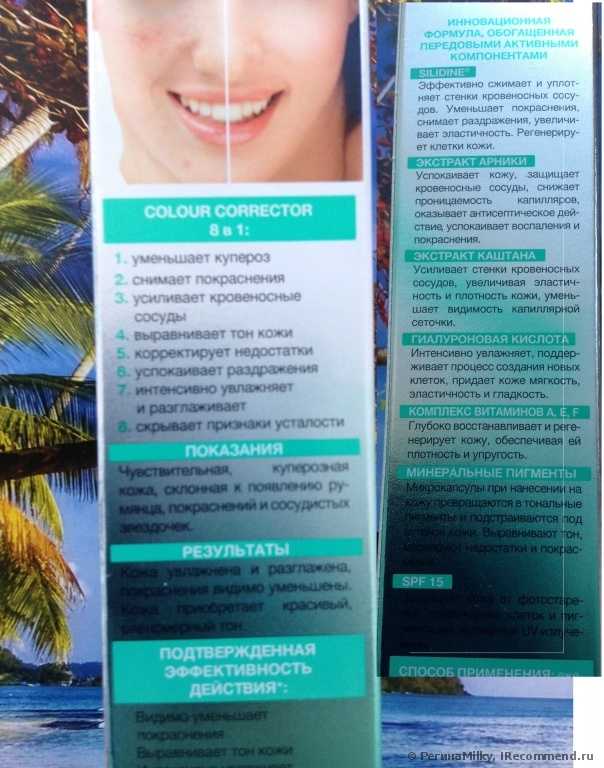

Когда мне понадобился легкий сонцезащитный крем для лица на лето, то в первую очередь я подошла к полкам с «Eeveline cosmetics», потому что это одна из любимых мной марок. Мое внимание привлек этот крем, потому что производитель обещает уменьшение купероза, увлажнение и смягчение кожи, защиту от УФА и УФБ лучей (SPF 15), коррекцию тона и мелких недостатков. Все эти обещания были кстати для летнего ухода. Крем не дорогой (142 руб), поэтому рискнула попробовать, не особо вчитываясь в состав. Дома вскрыла упаковку и познакомилась к кремом поближе.

При нанесении на кожу он легко распределяется без липкости или жирности. Действительно при растирании крем теряет свой зеленый оттенок и кожа приобретает цвет легкого загара (чем сильнее я растирала, тем темнее получался «загар»). Расширенные сосуды он слегка маскирует, тон кожи выравнивает. Если наносить крем специальным спонжем для тонального крема, то он ложится ровно тонким слоем, не приходится растирать и поэтому оттенок остается очень светлым, так лучше маскируются сосудики и покраснения. На лице крем не ощущается, эффекта маски нет. Не рекомендую наносить крем толстым слоем или в несколько слоёв, потому что при повторном растирании ранее нанесенного крема оттенок станет более темным. Я наношу крем один раз и хожу с ним весь день, кожа выглядит естественно, неприятных ощущений нет, вообще его не замечаю. Вокруг глаз его наносить нельзя, для этого я приобрела специальный крем для век Eveline с УФ защитой.

Одной тубы (30 мл) мне хватило почти на 2 месяца. За это время я заметила, что сосудики стали менее выраженными и краснота уменьшилась. Кожа разгладилась, уменьшились морщинки. Крем обладает матирующим эффектом и я перестала пользоваться пудрой. Правда в течении дня появляется легкий лоск, для снятия которого прикасаюсь слегка к лицу бумажной салфеткой.

Конечно для достижения более выраженного эффекта нужно больше времени, поэтому вчера купила новую упаковку крема, буду пользоваться все лето, о результатах сообщу. Крем достаточно стойкий, с минеральными пигментами, поэтому вечером убираю его мицеллярным раствором Eveline. На ночь тонким слоем наношу «Активный отбеливающий крем» Eveline. На фото видно, что в целом кожа стала светлее, пигментные пятна уменьшились. Днем пигмента не прибавляется благодаря сонцезащитным свойствам крема СС, а ночью кожа осветляется под действием отбеливающего крема.

Что касается состава, то крем действительно содержит экстракты лекарственных растений и витамины (см. в «Подробностях»), но они в самом конце списка ингредиентов, после 4 парабенов, касторового и кокосового масел), а в начале списка (первые 10 позиций) после воды значатся различные натуральные и синтетические эмоленты (вещества смягчающие и увлажняющие кожу, облегчающие распределение и нанесение крема). Поэтому одну звезду снимаю.

- Крем действительно работает.

- Успокаивает и увлажняет кожу.

- Уменьшает красноту и купероз.

- Выравнивает тон кожи и корректирует недостатки.

- Защищает от УФА и УФБ лучей.

- Легко наносится.

- Нет «эффекта маски».

- Достаточно стойкий, с минеральными пигментами.

- Благодаря гиалуроновой кислоте, разглаживает кожу и уменьшает морщинки.